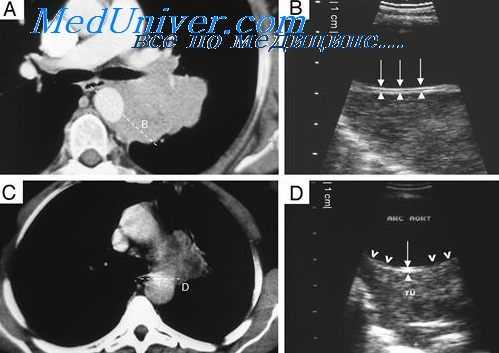

Прежде всего мы отбросили диагноз «тимома», с чем больной был направлен в институт. Против злокачественной тимомы свидетельствовало общее хорошее состояние больного без каких-либо признаков компрессии органов средостения (особенно крупных сосудов) при наличии огромной опухоли, занимающей почти все пространство от передней стенки грудной клетки до трахеи. Кроме того, на томограммах в прямой и боковой проекциях выявляется как бы конгломерат узлов, расположенных на различной глубине средостения, на что указывает и симптом «кулис».

Рентгенологическая картина с выраженным двусторонним поражением множества лимфатических узлов средостения на различной глубине давала больше оснований для диагноза лимфосаркомы.

При проведении курса рентгенотерапии оказалось, что данная опухоль довольно чувствительна к ионизирующему излучению, так как через 20 дней (после суммарной дозы в 4000 г) было отмечено значительное ее уменьшение, а через 40 дней (6000 г) она полностью исчезла.

Из литературы известно, что лимфосаркомы еще более рентгеночувствительны. Поэтому результаты рентгенотерапии при учете всех других симптомов позволяли нам остановиться на диагнозе лимфогрануломатоза, чувствительность которого примерно соответствует чувствительности опухоли в данном случае.

Биопсия периферического лимфатического узла подтвердила наш диагноз.

К сожалению, после, казалось бы, благополучного исхода лечения вскоре общее состояние больного резко ухудшилось, появился плевральный выпот, и больной умер через семь месяцев от начала клинического проявления заболевания.